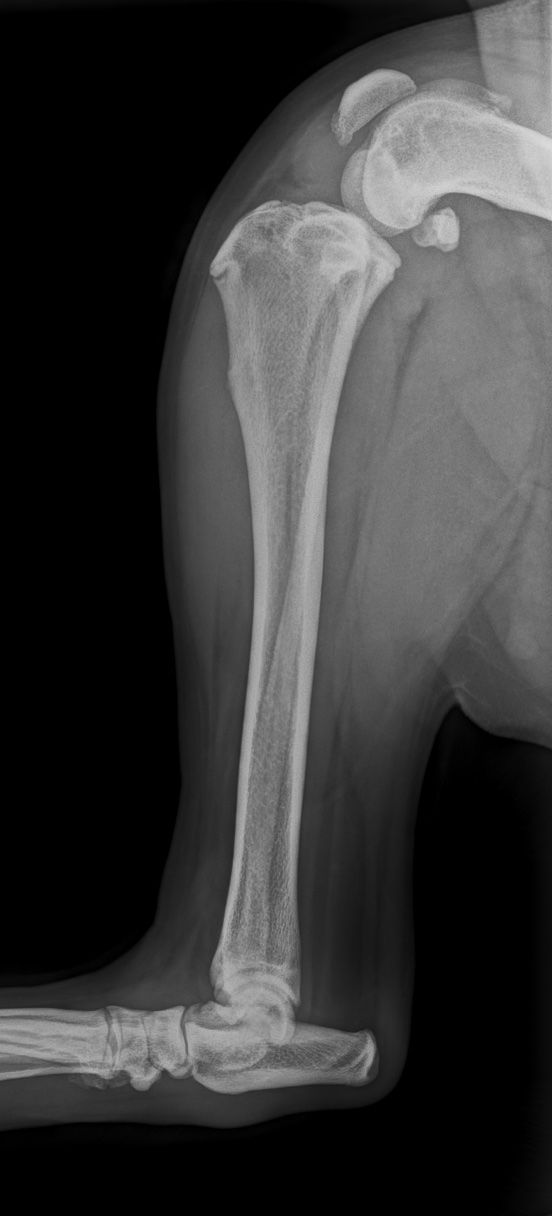

- Traumatologie & orthopédie : fractures complexes, lésions articulaires (coude/épaule/genou), évaluation pré-opératoire (TPLO, prothèse), suivi de consolidation.

La majorité des chirurgies orthopédiques nécessitent un bilan radiographique avant et après la chirurgie.